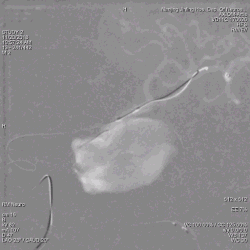

患者取平卧位,气管插管全麻,右侧股动脉穿刺,置入6F 70cm长鞘至左侧颈总动脉,5F Navien中间导管在Marksman引导下超选至动脉瘤近端,行3D旋转造影显示:左侧颈内动脉海绵窦段大型血栓性动脉瘤。

为什么要用到微导管张鑫教授:“球囊锚定微导管辅助到位”技术在Pipeline Flex治疗复杂动脉瘤手术中的应用_https://www.jmylbn.com_新闻资讯_第4张

3D旋转造影

显影部分动脉瘤大小约31.6*23.1mm,瘤颈宽6.4mm,载瘤动脉远端直径约为2.93mm,近端约为2.89mm。根据造影情况决定行血流导向装置置入术,选择Pipeline Flex 3.0mm*35mm。